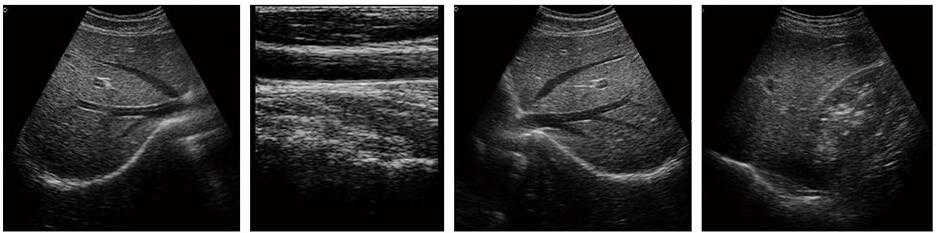

豐富的臨床應用

掃描方式:凸陣/線陣/微凸